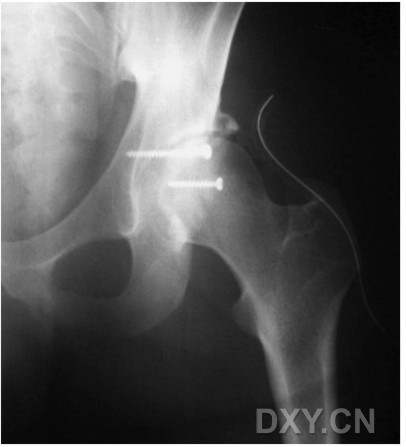

圖 2:男性,24歲,髖關(guān)節(jié)后脫位合并髖臼后壁骨折,傷后一小時(shí)內(nèi)進(jìn)行了股骨頭閉合復(fù)位。

圖-3:與圖1為同一患者,傷后4天行切開復(fù)位拉力螺釘內(nèi)固定術(shù)。